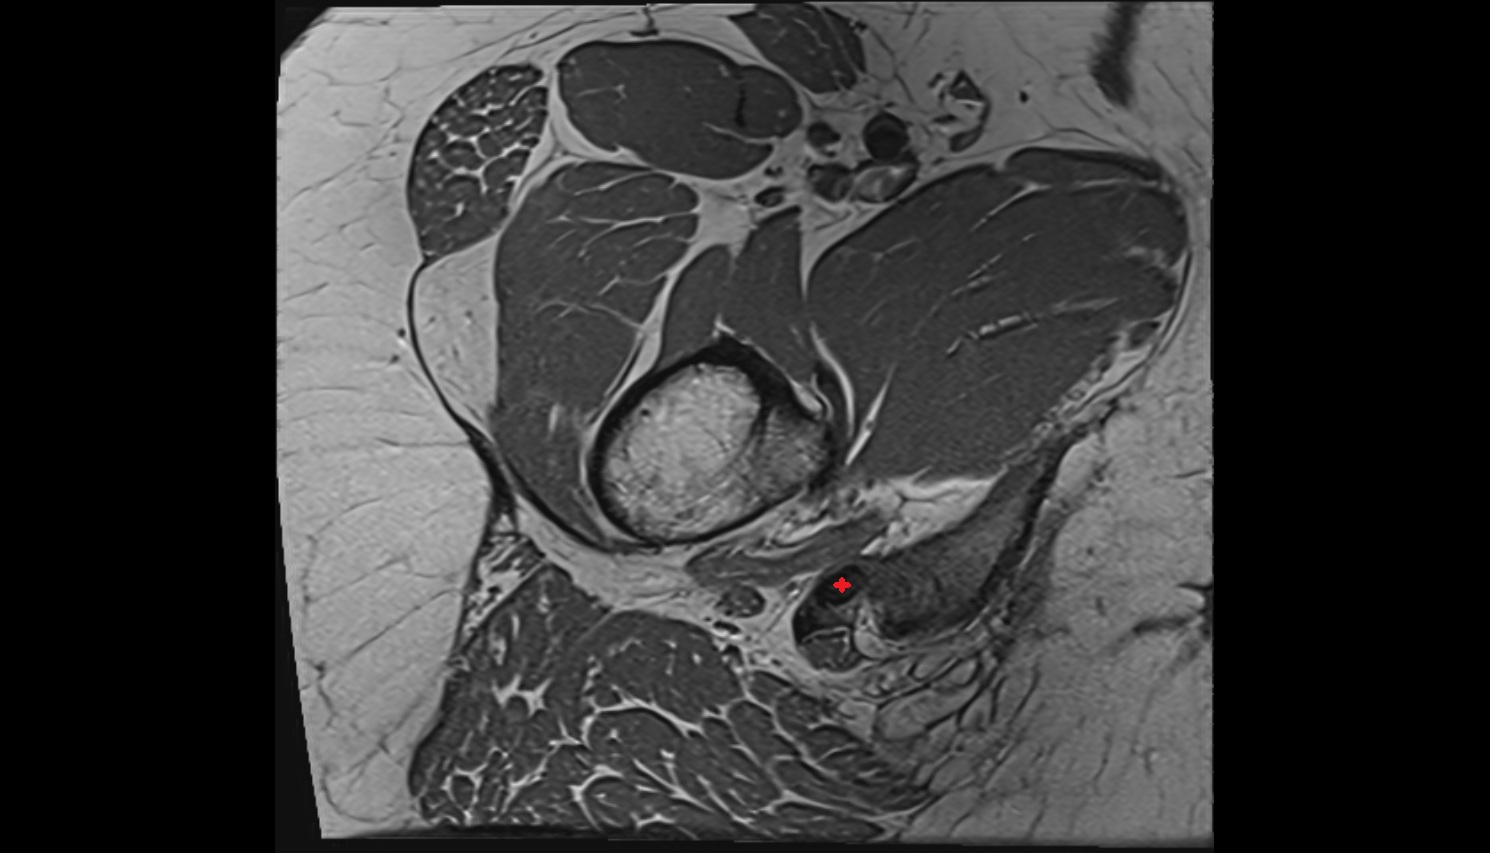

- Hip joint